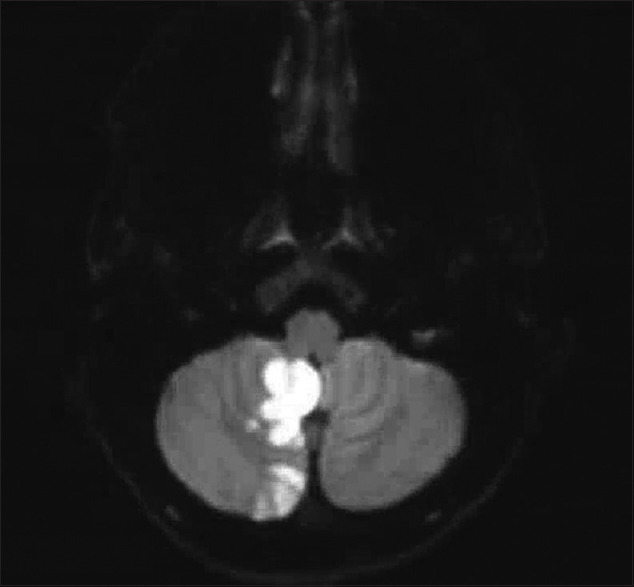

Results: A 47-year-old female presented with acute vertigo and gait imbalance. Magnetic resonance imaging showed AIS in the right cerebellum. CT chest confirmed a PAVM in the right lower lobe. Endovascular coil closure was performed. We identified 102 patients from 96 records. The mean age was 47.4 ± 17 years (67% female). Seventy percent had single AIS and 30% had multiple. The location was anterior circulation in 50%, posterior in 37%, and both in 13%. The most common arterial territory was middle-cerebral (51%), followed by posterior-cerebral (25%). PAVMs were mostly single (78%) and in the lower lobes (66%). Thirty-three had hereditary hemorrhagic telangiectasia (HHT) (33%).

Abstract Image